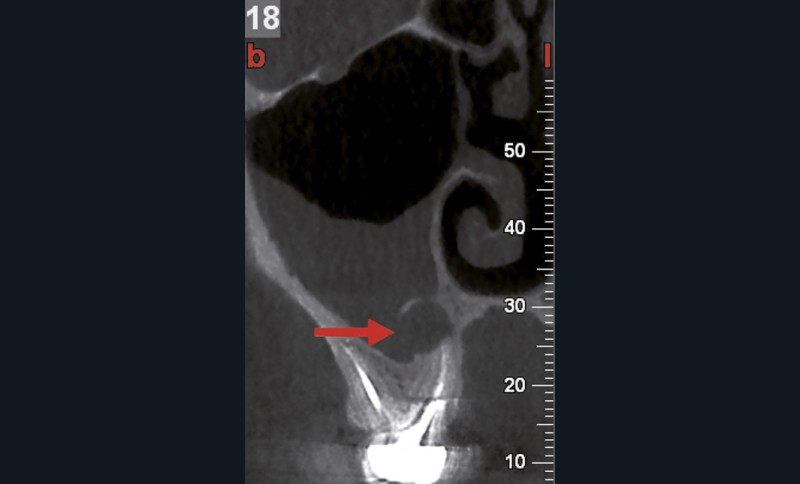

L’utilisation du scanner, et maintenant du CBCT, bouleverse l’idée très radiographique que nous avions du système canalaire.

En effet, la culture endodontique, fondée sur les critères radiographiques, a fait oublier les études de Hess et Zurcher (1925) qui mettent en évidence la complexité du système endo-canalaire [1]. Ce système présente une cavité principale (par exemple, le canal principal) ainsi que des canaux accessoires/latéraux. 25 % de ces microcanaux peuvent être interconnectés les uns aux autres, avec une densité plus importante de ramifications dans la région apicale du canal principal [2].

Rebondissant sur l’imagerie 3D et la mise en évidence des anatomies canalaires complexes, Peters, en 2001, décrit l’insuffisance instrumentale dans le traitement endodontique, et montre que 35 % des surfaces sont intactes après préparation canalaire correctement menée [18].

Endal, en 2011, montrait également, en utilisant le micro CT Scanner, l’insuffisance de nettoyage des isthmes inter-canalaires à nos techniques conventionnelles [19]. L’utilisation du laser Er:YAG devenait alors incontournable dans le nettoyage de ces isthmes et des zones non instrumentées (fig. 2 et 3).

Si l’étude de Peters [18] nous montre que l’instrumentation laisse 35 % du volume canalaire non instrumenté, Ricucci et Siqueira montrent que la préparation physico-chimique n’élimine que partiellement les tissus nécrotiques à l’entrée des canaux latéraux, des isthmes et des ramifications apicales, en laissant des tissus enflammés et infectés, en association avec des lésions apicales [29] (fig. 4 et 5).